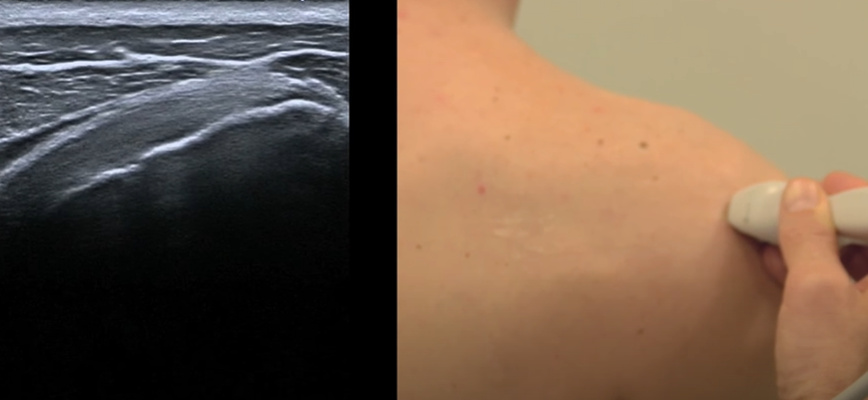

Face postérieure

Infra-épineux

- Position neutre du début

- Coupe longitudinale

- Insertion sur le tubercule majeur (face oblique)

Coupe lnogitudinale

Petit rond

- Position neutre du début

- Sagittal sur le tubercule majeur

- Insertion du petit rond sur la face verticale

Coupe axiale